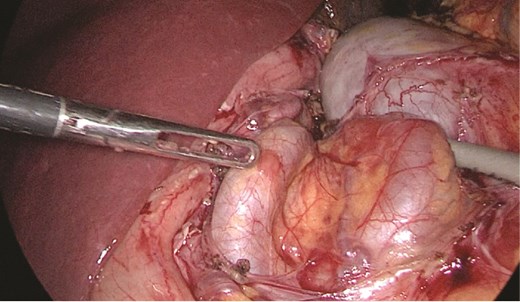

Multidisciplinary discussion was held to evaluate the most appropriate course of action for the patent condition, and the consensus was reached to pursue embolization as a first intervention. Embolization was performed by interventional radiology with no complications post-procedure, and the patient was optimized prior to her procedure. Patient was taken to the operating room in stable conditions. The spleen was enlarged around 20 cm. Inferiorly, the omentum and part of the transverse colon was attached to the spleen (Fig. 3), so we freed the omentum from the splenic tissue. The dissection continued until reaching short gastric vessels and entering the lesser sac (Fig. 4). Once the lesser sac was entered, the splenic vessels were identified (Figs 5 and 6), the splenic vein was hugely dilated with multiple collateral branching vessels at the hilum. Gaining posterior mobilization of the vein was challenging. The splenic artery was tortuous from the insertion around itself (Fig. 7). After complete mobilization of the fundus, we elected to divide each vessel starting with the splenic artery so we can achieve full mobilization of the vein (Fig. 9). After controlling the splenic artery, the splenic vein was dissected proximal to the splenic hilum (Fig. 8). It was hugely dilated and its wall is thickened secondary to AV fistula. It was difficult to achieve circumferential dissection, so we decided at that moment to convert to laparotomy to complete ligating the vein and to retrieve the specimen (Fig. 10a and b).

Stomach attached to the medial border of the spleen. Short gastric vessels.

Anterior portion of the splenic vein seen posterior to the stomach.